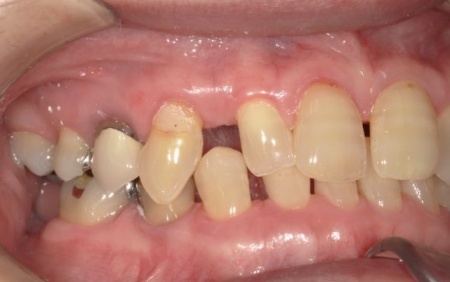

70代女性 歯根が割れた左下奥歯を抜きインプラントで噛み合わせを回復させた症例

「噛んだときに左下奥歯が痛むので診てほしい」とご相談いただきました。

レントゲン撮影を行って詳しく拝見したところ、左下奥歯(第1小臼歯)の歯根が割れていました。

しかし、根管治療では痛みが改善しなかったため、抜歯をする必要がありました。

まず、周辺組織に負担をかけないよう配慮しながら、慎重に左下奥歯(第1小臼歯)を抜きます。